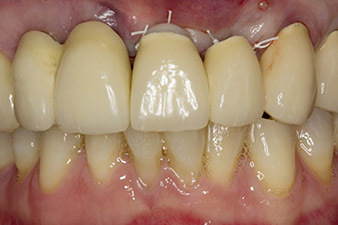

En la primera visita se trataron las piezas 21, 22 y 23, que presentaban bloqueo en las coronas colocadas hacía 19 años. Estas estaban unidas mediante una férula con los implantes de las posiciones 12/11 (figura 2). La imagen radiológica muestra una pérdida ósea horizontal alrededor de las piezas dentales 21 y 22 (figura 1).

Al extraer el bloque de las coronas estos dientes se habían extraído también de forma accidental. En la pieza dental 23 fracturada en sentido horizontal-coronal, se incorporó un muñón con pernos como tratamiento provisional. Se programó un puente de óxido de circonio en los implantes existentes en las posiciones 12 y 11 y dos nuevos implantes en las posiciones 22 y 23.

Después de la cicatrización primaria, los tejidos blandos se modelaron con ayuda del puente con base reconstruida. Dos meses después, se procedió a la exposición del área con una incisión de la cresta maxilar en sentido ligeramente palatino (figura 2).

En el caso clínico presentado, la situación se resolvió en la primera intervención con un implante en la posición 22, así como con otro en la posición de la pieza dental 23 extraída en el transcurso posterior. El segundo implante se realizó después de la osteointegración del implante 22. El puente remodelado se volvió a colocar hasta la cicatrización del implante 23 y la conformación para la prótesis definitiva. Las ventajas de este procedimiento escalonado son una capacidad de carga segura de los implantes y una buena maduración de los tejidos duros y blandos (5).